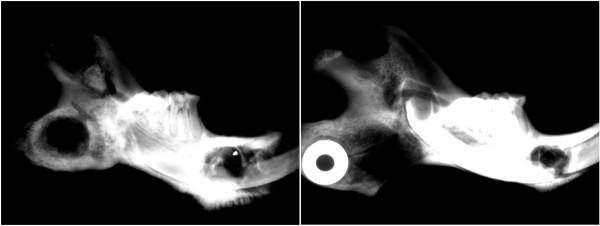

The ability of irradiated tissue to support bony growth remains poorly defined, although there are anecdotal cases reported showing mixed results for the use of mandibular distraction osteogenesis after radiation for head and neck cancer. Many of these reports lack objective measures that would allow adequate analysis of outcomes or efficacy. The purpose of this experiment was to utilize a rat model of mandibular distraction osteogenesis after high dose and highly fractionated radiation therapy and to evaluate and quantify distracted bone formation under these conditions. Male Sprague-Dawley rats underwent 12 fractions of external beam radiation (48 Gray) of the left mandible. Following a two week recovery period, an external frame distractor was applied and gradual distraction of the mandible was performed. Tissue was harvested after a twenty-eight day consolidation period. Gross, radiologic and histological evaluations were undertaken. Those animals subjected to pre-operative radiation showed severe attenuation of bone formation including bone atrophy, incomplete bridging of the distraction gap, and gross bony defects or non-union. Although physical lengthening was achieved, the irradiated bone consistently demonstrated marked damaging effects on the normal process of distraction osteogenesis. This murine model has provided reliable evidence of the injurious effects of high dose radiation on bone repair and regeneration in distraction osteogenesis utilizing accurate and reproducible metrics. These results can now be used to assist in the development of therapies directed at mitigating the adverse consequences of radiation on the regeneration of bone and to optimize distraction osteogenesis so it can be successfully applied to post-oncologic reconstruction.

虽然有一些轶事病例报告显示,头颈部癌症放射治疗后使用下颌骨牵引成骨术有混合结果,但辐射组织支持骨生长的能力仍未得到明确界定。这些报告中的许多都缺乏客观的衡量标准,无法充分分析结果或疗效。本实验的目的是利用大剂量和高分割放射治疗后下颌骨牵引成骨的大鼠模型,并在这些条件下评估和量化牵引骨的形成。雄性 Sprague-Dawley 大鼠接受左下颌骨的 12 次外束放射治疗(48 Gray)。经过两周的恢复期,应用外固定架牵开器,并逐渐牵开下颌骨。在 28 天的巩固期后采集组织。进行了大体、放射学和组织学评估。那些接受术前放射治疗的动物表现出骨形成的严重衰减,包括骨萎缩、牵引间隙不完全桥接以及明显的骨缺损或骨不连。尽管实现了物理延长,但辐射后的骨骼始终对牵引成骨过程中的正常骨改建过程产生明显的损伤作用。该鼠模型为高剂量辐射对牵张成骨中骨修复和再生的损伤作用提供了可靠的证据,利用准确和可重复的指标。这些结果现在可用于帮助开发针对减轻辐射对骨再生的不利影响的治疗方法,并优化牵张成骨术,以便成功应用于肿瘤后重建。